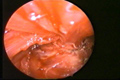

العمليات الجراحية التصويرية بالفيديو المنظاري

Videoendoskopik (Kapalı) Cerrahi

Paratiroidektomi

Tiroidektomi

Ameliyat'tan Görüntüler